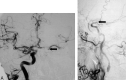

Background and purpose: Two large trials indicated that endarterectomy was less beneficial for symptomatic patients with internal carotid artery (ICA) near occlusion than for patients who had severe stenosis without near occlusion. Near occlusions complicate ratio calculations of ICA stenosis and require attention to detail for identification. The goal is to provide diagnostic criteria, illustrate identifying features, estimate accuracy of identification, and assess prognosis for patients with near occlusion.

Methods: We re-reviewed 1216 patients with severe (> or =70%) stenosis on angiography in the North American Symptomatic Carotid Endarterectomy Trial and European Carotid Surgery Trial. One of 5 (n = 262) had 2 or more criteria for near occlusion: (1) delayed cranial arrival of ICA contrast compared with external carotid artery (ECA); (2) intracranial collaterals seen as cross-filling of contralateral vessels or ipsilateral contrast dilution; (3) obvious diameter reduction of ICA compared with opposite ICA; or (4) ICA diameter reduction compared with ipsilateral ECA.

Conclusion: It is crucial to identify near occlusions on vascular imaging. Although it still is reasonable to consider endarterectomy for these patients, the benefit is muted.